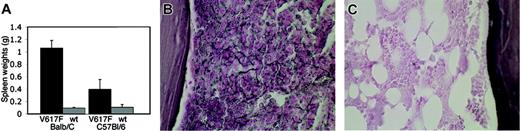

Splenomegaly and reticulin fibrosis in Jak2V617F mice after BM transplantation. (A) Bar graphs indicate an 11-fold increase in spleen weight in Jak2V617F Balb/c compared with Jak2wt Balb/c animals and an approximately 4-fold increase in spleen weight in Jak2V617F C57Bl/6 compared with Jak2wt C57Bl/6 mice. (B) Moderate to marked diffusely increased reticulin fibrosis in BM of Balb/c mice that had received transplants of Jak2V617F 4.5 weeks after transplantation, which was absent in Jak2wt BM (C).

Freshly harvested BM was transduced with MSCV-IRES-EGFP vectors containing Jak2wt, Jak2V617F, or no insert, respectively, and was transplanted into lethally irradiated Balb/c or C57Bl/6 recipient mice. Four weeks after transplantation, Jak2V617F-transduced animals had developed elevated HCTs (mean .74, n = 22) with no apparent strain-specific differences (P = .49), whereas both strains of mice that received Jak2wt-transduced BM had normal HCTs (Table 1). Jak2V617F-transduced mice had elevated HCTs for as long as 20 weeks (Figure S3). At the time of humane killing, Jak2V617F Balb/c mice (n = 16) had marked splenomegaly and higher average spleen weights (1.06 g) than Jak2wt-transduced mice (n = 10), whose average spleen weight was 0.1 g (Figure 1A). In addition, Balb/c and C57Bl/6 mice that received BM transduced Jak2V617F had leukocytosis and splenomegaly, in contrast to mice that that received BM transduced with Jak2wt, but the degree of leukocytosis was markedly higher in the Balb/c mice (mean, 112 × 109/L; n = 22) than in the C57Bl/6 mice (mean, 20 × 109/L; n = 18). WBC counts were abnormally elevated in only 3 of 18 animals (Table 1).

Histopathologic analysis of BM from Jak2V617F mice showed a prominent population of maturing myeloid cells with mildly to moderately increased numbers of megakaryocytes, including large, atypical forms occurring in occasional clusters and showing emperipolesis of neutrophils in megakaryocyte cytoplasm (Figure 2C). In contrast, Jak2wt-transduced BM sections showed preserved marrow architecture with normal ratios of myeloid to erythroid elements and unremarkable megakaryocytes (Figure 2D). Spleen sections from Jak2V617F Balb/c mice exhibited complete effacement of normal splenic architecture and expansion of red pulp by an atypical population of maturing myeloid forms, erythroid elements, and clusters of dysplastic megakaryocytes (Figure 2E,G) compared with Jak2wt spleens, in which was found preserved normal splenic architecture with unperturbed red and white pulp (Figure 2F,H). Liver sections of Jak2V617F mice demonstrated extensive amounts of extramedullary hematopoiesis with clusters of maturing myeloid cells, occasional dysplastic megakaryocytes, and erythroid elements, in contrast to normal liver histopathology in Jak2wt animals (Figure 2I-L). We also observed moderately to markedly increased diffuse reticulin fibrosis in the BM of Jak2V617F Balb/c mice, but there was no fibrosis in the C57Bl/6 background or in animals of either background that received BM transduced with Jak2wt (Figure 1B-C).